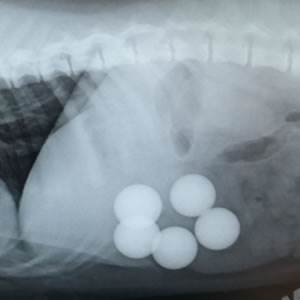

Vets at Croydon PDSA Pet Hospital took an X-ray – and were stunned to see another four balls in seven-month-old Lucky’s stomach.

Emergency surgery was carried out to remove the balls, which could have caused a fatal blockage. Lucky was monitored overnight, but thankfully he’d bounced back to health and was able to go home the following day.